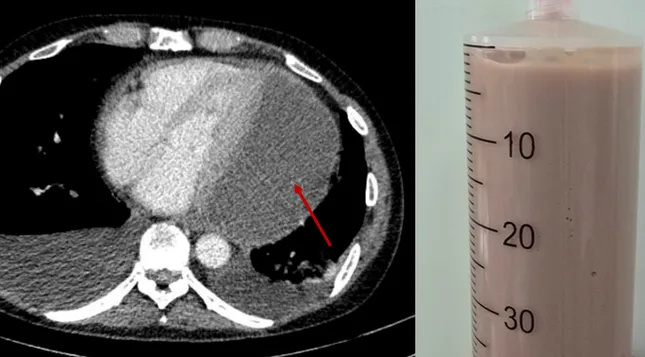

Tình trạng bệnh diễn tiến âm thầm nhưng ngày càng nghiêm trọng. Khi đến Bệnh viện Nhân dân 115, bệnh nhân trong trạng thái suy kiệt toàn thân, phải thở oxy liều cao, phù nề toàn thân, huyết áp tụt và mạch nhanh. Các bác sĩ nhanh chóng thực hiện siêu âm tim và phát hiện một khối dịch lớn gần 11cm bao quanh tim. Ổ mủ đặc quánh này gây chèn ép tim nghiêm trọng, khiến tim gần như không thể co bóp, đẩy bệnh nhân vào nguy kịch.

Nhận thấy nguy cơ tử vong cấp tính, các bác sĩ của nhiều chuyên khoa tại Bệnh viện Nhân dân 115 đã khẩn trương hội chẩn và thống nhất chỉ định chọc hút dịch mủ màng ngoài tim ngay tại giường bệnh dưới hướng dẫn siêu âm. Đây là thủ thuật khó, do dịch mủ đặc nằm sâu và sát các cấu trúc nguy hiểm của tim. Sau quá trình thao tác cẩn trọng, ê-kíp đã hút ra được 500ml mủ đặc, nhanh chóng giải phóng áp lực chèn ép, giúp tim bắt đầu co bóp trở lại.